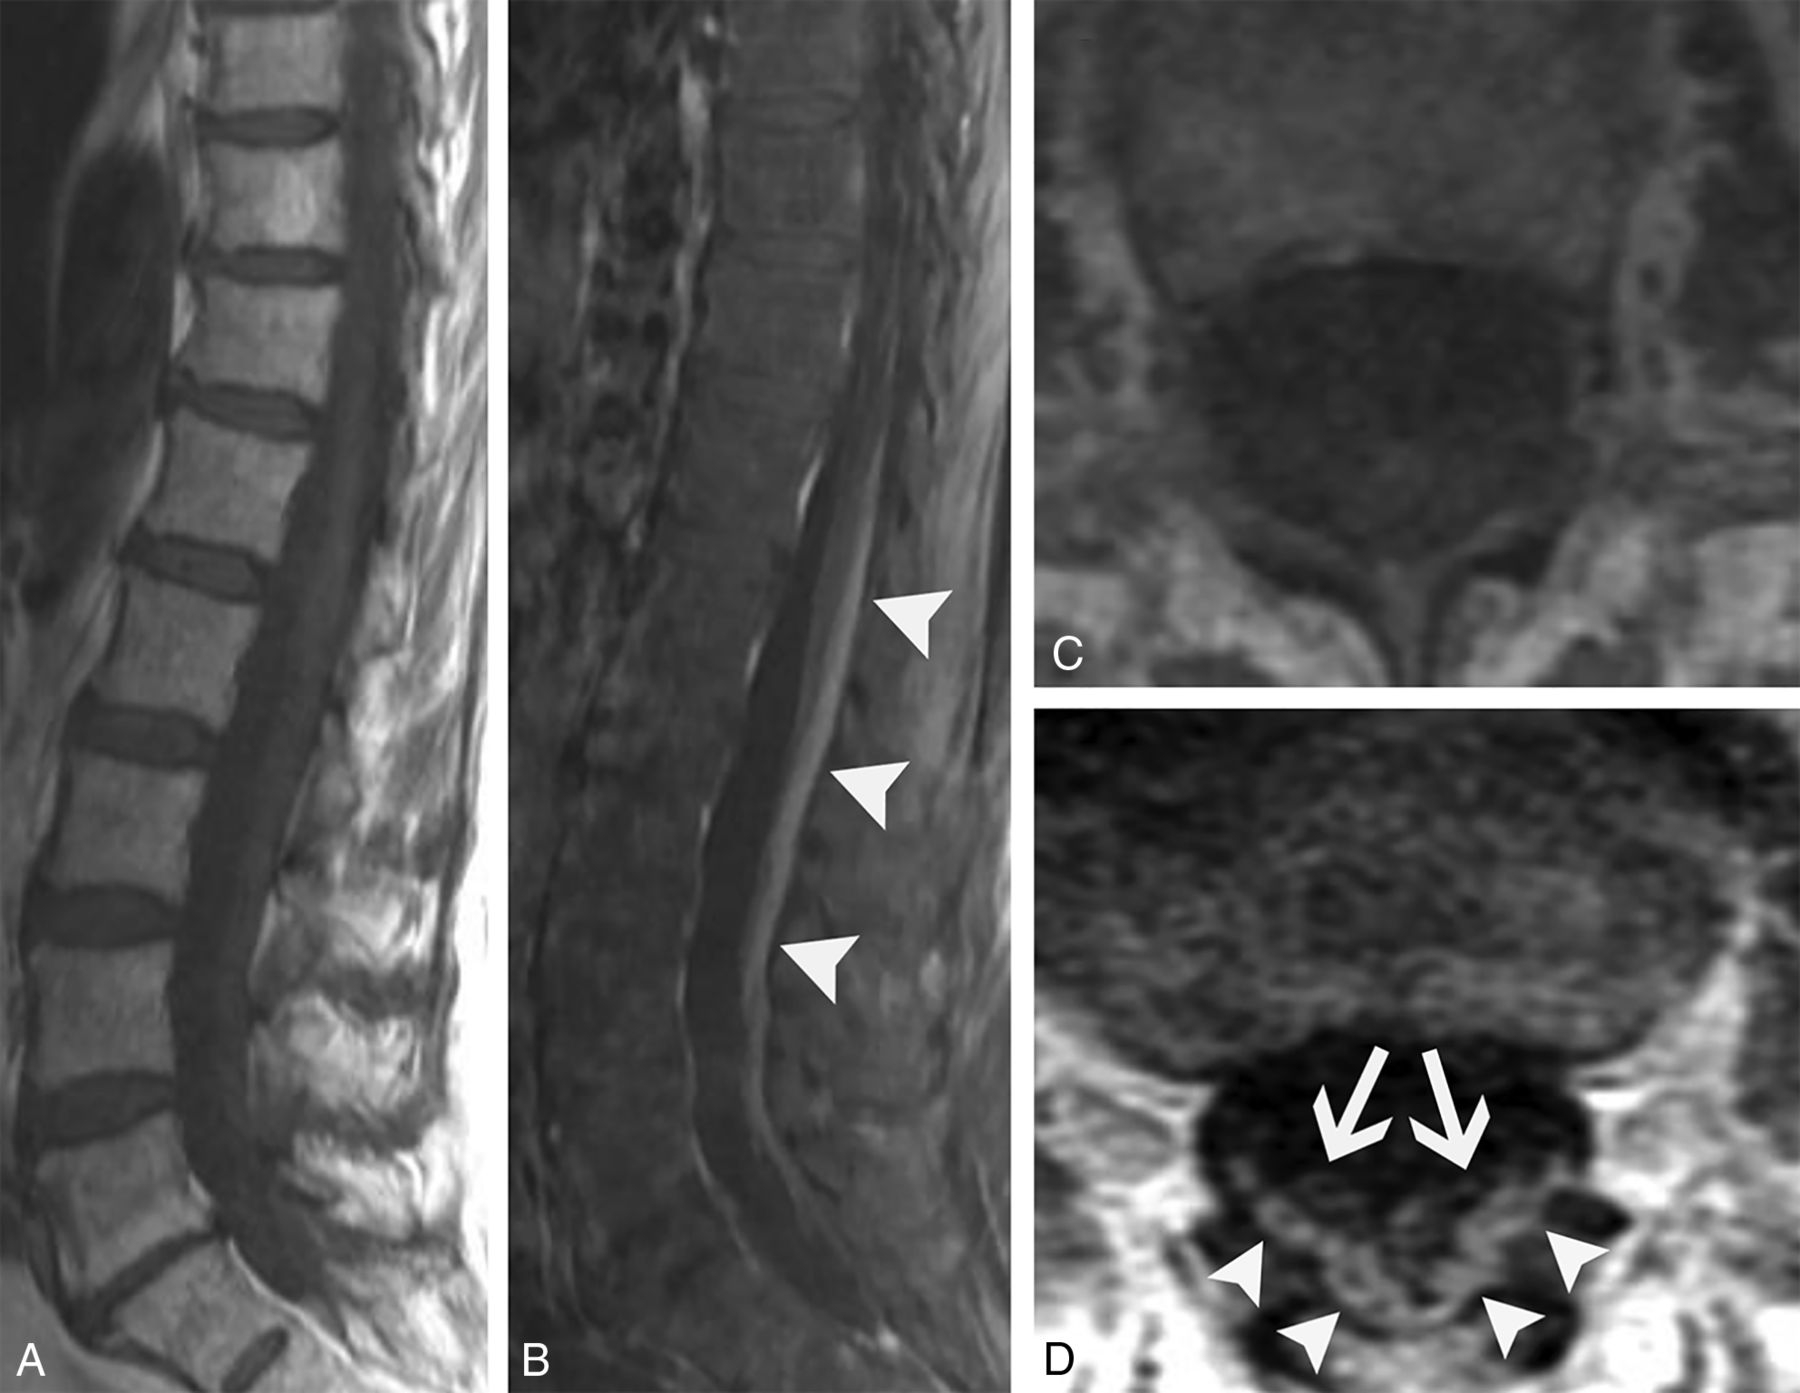

Reports of imaging findings of paraneoplastic polyneuropathy involvement are scarce. To our knowledge, there are only 5 published cases of paraneoplastic polyneuropathy showing cauda equina abnormalities. These have demonstrated variable patterns of enhancement, with 2 patients having ANNA-1 positivity.27,29-32 We have found that enhancement can predominantly involve the dorsal (Fig 8) or ventral nerve roots (Fig 9), and the pattern of enhancement does not always correlate with symptoms. The clinical presentation can frequently mimic Guillain-Barré syndrome with a similar rapidly ascending weakness (Fig 8). Additionally, polyneuropathy may be seen with osteosclerotic multiple myeloma in the setting of POEMS syndrome (polyneuropathy, organomegaly, endocrinopathy, monoclonal plasma proliferative disorder, skin changes).33 Although POEMS syndrome is not always described among the classic forms of PNS, many authors consider its peripheral nerve involvement to be paraneoplastic. The presence of sclerotic bone lesions and peripheral nerve root enhancement are the most important imaging features to suggest POEMS syndrome (Fig 10).

Paraneoplastic polyneuropathy mimicking Guillain-Barré syndrome. A 69-year-old woman presented with rapidly progressive ascending weakness and paresthesias. CSF analysis was remarkable for albuminocytologic dissociation, and the patient was initially diagnosed with Guillain-Barré syndrome. Sagittal T1-weighted pre- (A) and postcontrast (B) and axial T1-weighted pre- (C) and postcontrast (D) images from the patient’s lumbar spine MR imaging show enhancement of the predominantly dorsal cauda equina nerve roots (B–D, arrowheads). There is relative sparing of the ventral nerve roots (D, arrows), somewhat atypical for Guillain-Barré syndrome. The patient’s CSF was later found to be ANNA-1/anti-Hu antibody positive, and she was ultimately found to have small cell lung cancer.

Ventral predominant paraneoplastic polyneuropathy. A 29-year-old man with a history of mediastinal seminoma presented with progressive lower extremity weakness and frequent falls over months. Lumbar puncture showed elevated CSF IgG. Serum and CSF were positive for Kelchlike protein 11 autoantibodies. Sagittal T1-weighted pre- (A) and postcontrast (B) images, as well as corresponding axial T1-weighted pre- (C) and postcontrast (D) images from his lumbar spine MR imaging demonstrate smooth enhancement of the cauda equina nerve roots with a predilection for the ventral roots (B and D, arrows). There is clear sparing of the dorsal roots (B and D, arrowheads). He was diagnosed with paraneoplastic polyneuropathy and had mild symptomatic improvement with numerous immunosuppressive agents.

POEMS syndrome. A 50-year-old woman presented with weakness, burning, and tingling in her extremities that had waxed and waned over 4 years. Axial T1-weighted pre- (A) and postcontrast (B) images from her lumbar spine MR imaging show diffuse enlargement and enhancement of the cauda equina nerve roots (B, arrowheads). Axial CT (C) and fused FDG-PET/CT (D) images show a non–FDG-avid lumbar vertebral sclerotic lesion (C and D, arrowheads) and an adjacent mildly FDG-avid sclerotic lesion (C and D, arrows). After additional work-up, she was diagnosed with osteosclerotic multiple myeloma, which is characterized by osteosclerotic lesions with variable FDG avidity. Her MR imaging findings were ultimately attributed to polyneuropathy in the setting of POEMS syndrome.

Differential diagnoses for paraneoplastic polyneuropathy mainly include Guillain-Barré syndrome and infection. Guillain-Barré syndrome classically, but not always, has ventral predominant nerve enhancement. Chronic inflammatory demyelinating polyneuropathy could be considered but is less likely to show any enhancement and would have more prominent nerve enlargement. Entities such as neurosarcoidosis or leptomeningeal carcinomatosis tend to have more nodular enhancement. Ventral cauda equina enhancement has also recently been described in association with cord infarct.34